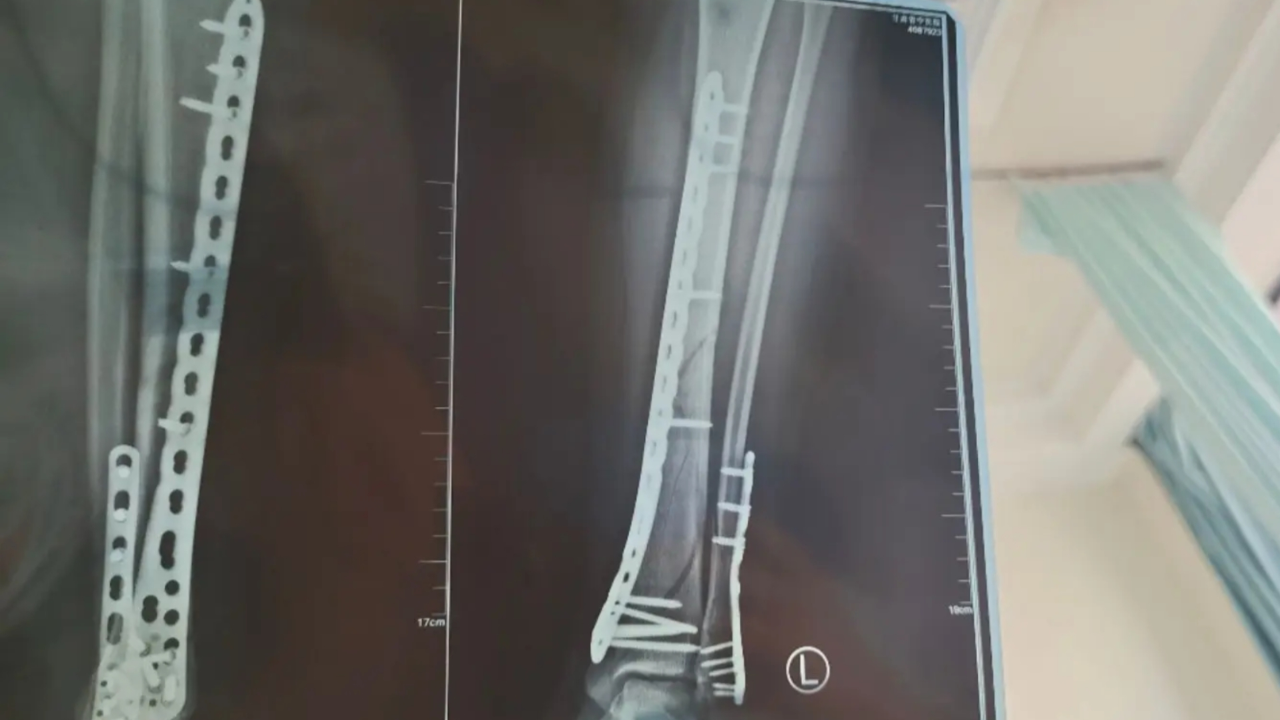

女子穿7cm厚洞洞鞋崴脚,致左腿粉碎性骨折!当事人:完全康复需3个月